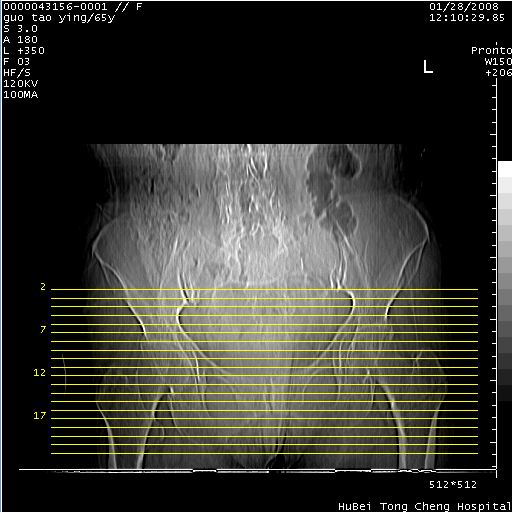

以下是引用黑白光影在2008-1-30 13:22:00的发言:[br]支持左耻骨骨折。[br]未见骶骨骨质明确破坏改变。[br]经楼主提示(勿局限于外伤)。考虑为右侧腹股沟直疝。[br][br][br][br]